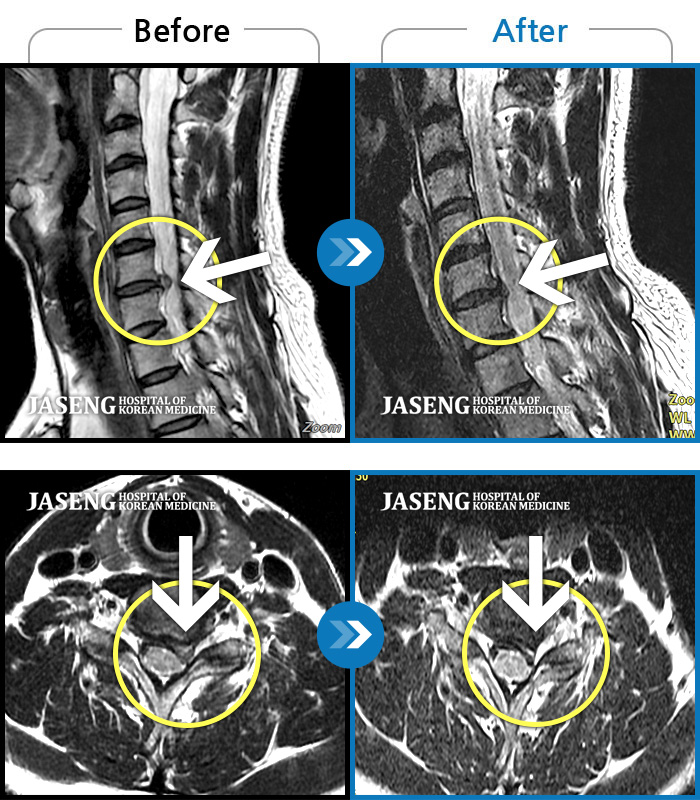

ȯںп  Ǹ   ǿ ԿǾ, ο  ġ  ۿ     Ƿ   ġḦ Ͻñ ٶϴ.